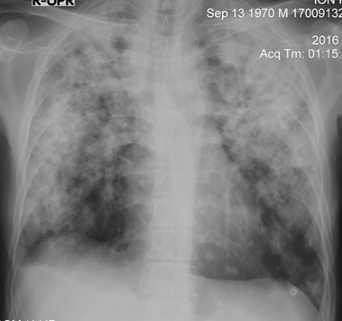

Rx toracică, incidență P-A

DESCRIERE:

pe tot teritoriul pulmonar, bilateral → opacități nodulare multiple de dimensiuni variabile, intensitate medie-mare, omogene, cu contur net

distribuție anarhică

blocuri adenopatice la niv. hilurilor pulmonare

DX: MTS pulmonare hematogene

DD:

hidatidoză - dimensiuni mai mari

bronhopneumonie - contur neregulat, neomogene, distribuție bazală